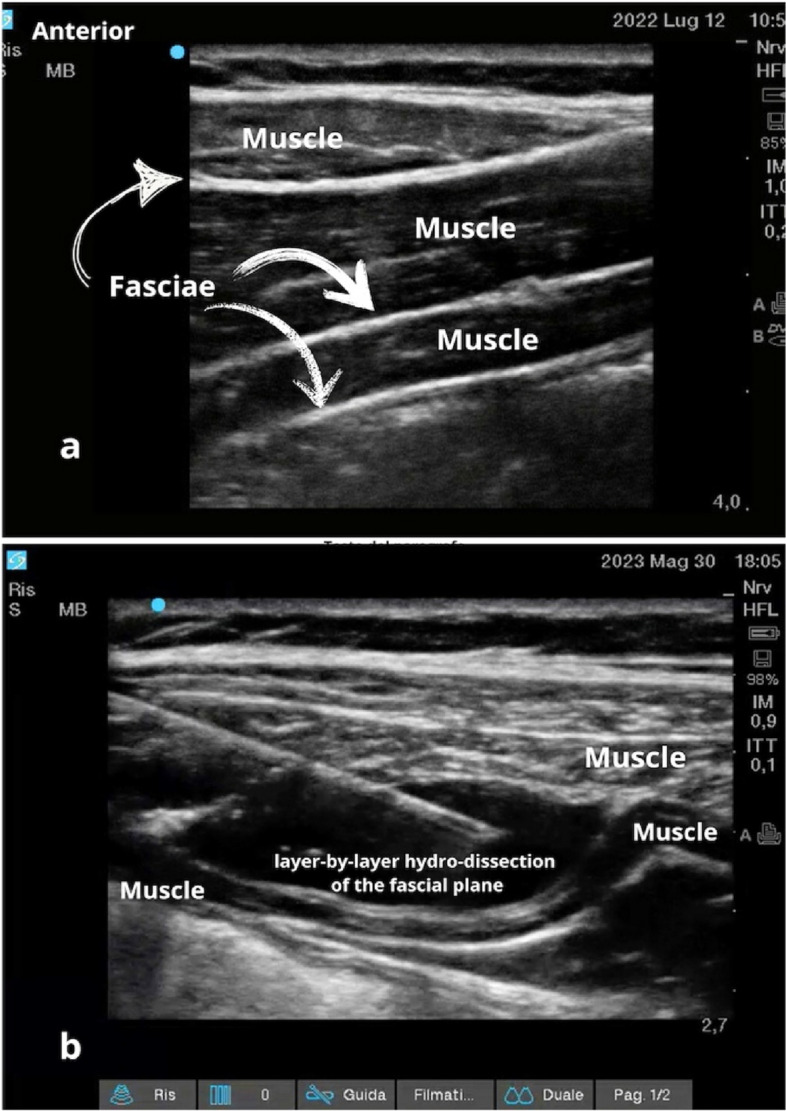

Background: Recent studies have unveiled the intricate and distinctive nature of fascia, no longer regarding it solely as a muscle container. Recent research highlights its complex innervation and structure, signifying its significance in chronic pain pathways.

Methods: We conducted a systematic literature search (updated on February 2024) to evaluate the role of fascial plane blocks in chronic pain treatment. All article types (randomized clinical trials, prospective and retrospective observational studies along with case reports and case series) were deemed eligible for inclusion if they referenced "fascial plane blocks" for the control of chronic pain conditions (persistent post-surgical, neuropathic, musculoskeletal-myofascial and cancer-related) and were published between 2010 and February 2024.

Results: The search revealed an increasing evidence in the literature for the implementation of fascial blocks in chronic pain management, although still heavily limited to case reports or series.

Conclusion: With the integration of ultrasound technology and a deeper understanding of their mechanisms of action, the fascial plane blocks continue to broaden their application also in chronic pain management, as a part of a multimodal strategy or as an alternative to conventional drugs or opioids.